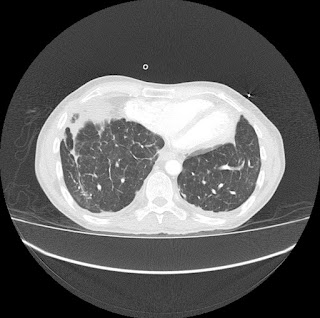

Escanografía